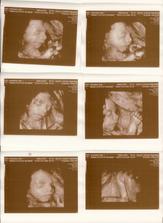

26.8.11 Emicka je uzasna🙂)) cca 25cm, 327g, mame fotecku i dvd, krasne se hybala,. zivala.. no nadhera🙂

13.10.2011 Dle dnesniho 4D ma Emis 922g, kolik cm jsme se nedozvedeli, pry se to ted urcuje spatne.. Jinak to vypada, ze nosanek bude mit po tatinkovi a pusinku po mamince;) Moc se ji hybat nechtelo, spinkala, obcas se pohla, dala rucicky pred oblicej, nozku pres nozku a taky se usmala🙂)

1.11.11 ko 29+1, Emisatko ma 1200g, dle biometrie je o cca tyden mensi (28+2), ale nozky ma delsi:D pry je porad v norme, plodovky ma dost, v cekarne radila, kdezto na utz mela pulnoc🙂 odebrana krev, CS 0, dalsi ko 22.11. a k 21.11. nastup na materskou🙂